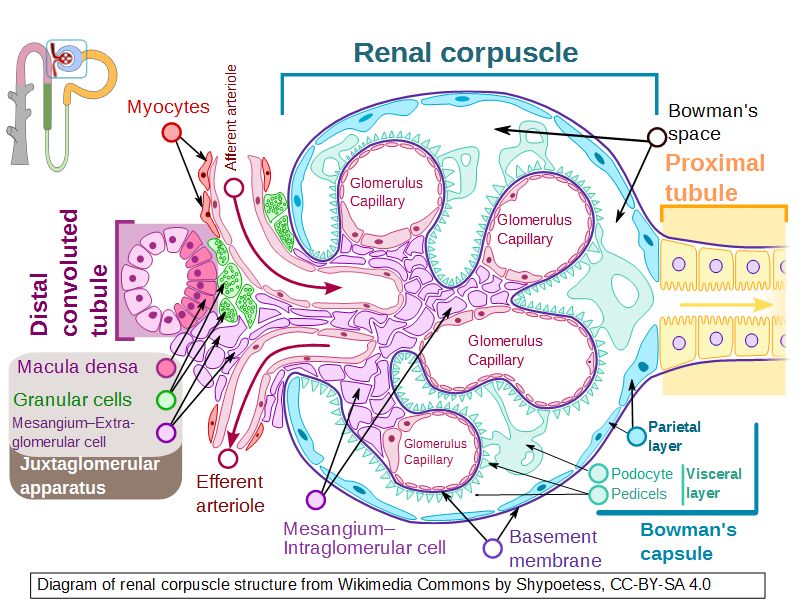

Renal corpuscle

- Tuft of capillaries

- grow into

- Blind end of nephron

- Several layers of epithelium

- Two sides

- Vascular pole

- Tubular pole

Blood flow

- Efferent arteriole

- Smooth muscle in media

- Capillaries

- Fenestrated

- Afferent arteriole

- Smooth muscle in media

Epithelium layers

- Capillary endothelium

- Visceral layer of epithelium

- Podocytes

- Resting on glomerular basement membrane

- Capsular space

- Parietal layer of epithelium

- Simple squamous epithelium

Juxtaglomerular complex

Area where distal convoluted tubule return to glomerulus and pass through the notch between the afferent and efferent arterioles. Modification of the wall of the tubule and afferent arteriole and presence of specialised cells in the connective tissue.Modifications

- Distal convoluted tubule

- Macula densa

- Narrow epithelial cells

- Nuclei densely packed

- CT cells

- Laci cells

- Similar to mesangial cells

- Afferent arteriole

- Modified smooth muscle cells

- Juxtaglomerular cells

- Secretory function

Capillaries

- Supported by

- Mesangial cells

- Mesangial matrix

- Phagocytic

- Maintain basement membrane

- Remove macromolecular deposits

Mesangial cells

- Around capillary loops at vascular pole

- Phagocytic

- Maintain basement membrane

- Remove macromolecular deposits

Podocytes

- Visceral layer of epithelium

- Protrude into capsular space

- Attached to basement membrane

- Long cytoplasmic extensions

- Primary processes

- Secondary processes

- Podocyte feet

- Tightly spaced

- Filtration slits 20 - 30 nm wide